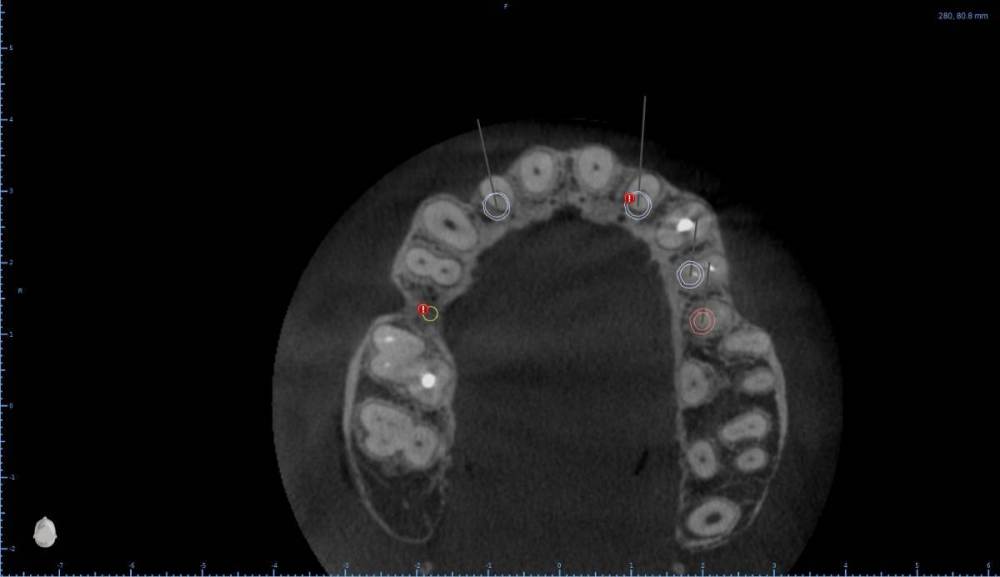

Женька Опубликовано 6 августа, 2022 Поделиться Опубликовано 6 августа, 2022 В общем планируется большая (по крайней мере для меня) работа. Вот такой товарищ у нас. Делали бы НКР в области 2.5з? или поставили бы чисто по кости, а оголённый участок закрыли присыпкой и мембраной? Также вопросы по двойкам имеются. Бугор есть, сразу оговорюсь, правда только с одной стороны. Также не понятно пока "как его правильно готовить" этот бугор, чтобы закрыть такие дефекты вестибулярной пластинки. Скрины постарался нарезать по максимуму. Там ещё будет ортодонтия конечно же. Интрузии, движения всякие и тд) Да, знаю, что планировать без цифрового гипса неправильно, но что имею. Ссылка на комментарий

Irouil Опубликовано 6 августа, 2022 Поделиться Опубликовано 6 августа, 2022 Если будет ортодонтия, то не проще ли вытянуть двойки чтобы вырастить ткани? ИДР тут нужен основательный очень, винты придётся крутить тоже очень длинные В области премоляра не вижу смысла что-то графтить, если хочется чего-то натолкать - можно стружки со сверла упаковать в дефект, но имхо не обязательно. А если сместить винт небно и чуть аннулировать, преп только пилотным и дальше конденсировать... ну Вы поняли 1 Ссылка на комментарий

Женька Опубликовано 6 августа, 2022 Автор Поделиться Опубликовано 6 августа, 2022 (изменено) @Irouil ортопед вряд ли согласится на такое. Может тогда проще пойти отсроченно? Удалить, кюретаж, губку в лунки и мэриленд (каппа с зубами) на 3 месяца. А потом уже выдумывать пластики по факту новой КТ? Винты 14мм максимум что есть По премоляру вот тоже думаю, что игра не стоит свеч. А двойки... признаться я уже ортопеду сказал, что отсрочено пойдём... хотя конечно пока всё ещё раздумываю Изменено 6 августа, 2022 пользователем Женька Ссылка на комментарий